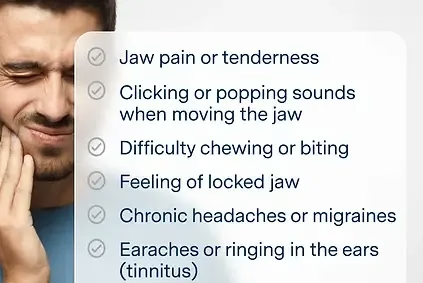

Symptômes des douleurs de la mâchoire

- Douleurs en avant de l'oreille

- Douleurs au niveau de la mâchoire

- Douleurs au niveau des muscles masticateurs

- Maux de tête

- Bruits dans l'articulation (claquement, crissements)

- Limitation d'ouverture de bouche

- Acouphènes

Quels sont les symptômes des troubles de l'ATM ?

Les symptômes incluent : douleurs en avant de l'oreille, limitation d'ouverture buccale, bruits articulaires (claquements, crissements), maux de tête, douleurs cervicales associées et parfois des acouphènes. Ces symptômes peuvent être unilatéraux ou bilatéraux.